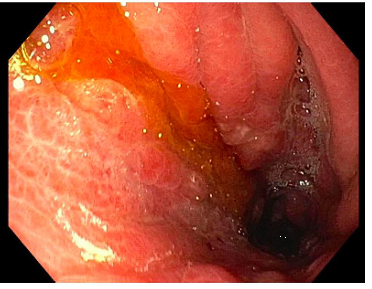

At this stage, given multiple inconclusive investigations, the decision was made to proceed to a diagnostic laparoscopy; this revealed extensive lesions on the peritoneal surface suspicious for peritoneal carcinomatosis (Figure 3). Excisional biopsies were suggestive of metastatic adenocarcinoma of gastrointestinal origin. Gastroscopy was then performed which demonstrated friable and nodular gastric mucosa, the biopsies of which confirmed diffuse gastric adenocarcinoma (Figure 4). Given her extensive peritoneal disease, the patient was referred to medical oncology for palliative chemotherapy.

Figure 4 Gastroscopy demonstrating an area of congested, friable and nodular gastric mucosa at the greater curvature.